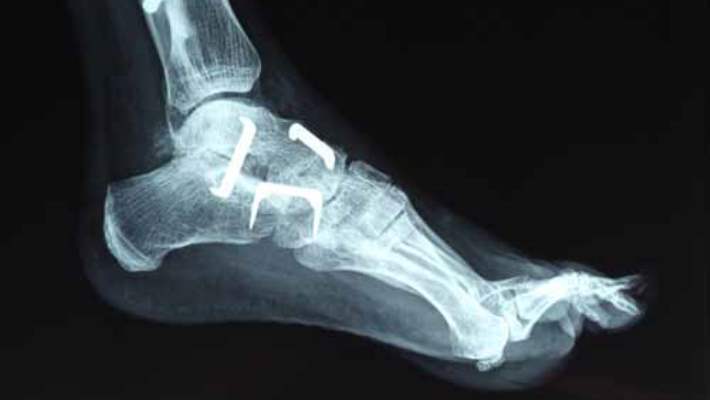

Birçok kemik mahmuzu hiçbir ağrı veya belirtiye neden olmaz. Genellikle röntgen veya başka bir görüntüleme tekniğinde veya başkaca bir tıbbi sorunla ilgili testlerde tesadüfen tespit edilir.

Eklem ağrısı yaşıyorsanız, doktorunuz ağrınızı daha iyi anlamak için sizi fiziksel muayeneden geçirecektir. Ağrının tam olarak nereden geldiğini anlamak için eliyle ekleminizi kontrol edebilir. Bazen doktorlar eliyle bir kemik mahmuzunu hissedebilir, bununla birlikte bir sivilcenin içinde olan mahmuzları hissetmek kolay değildir.

Doktorunuz teşhisi kesinleştirmek için eklemlerinize ve kemiklerinize bakabileceği bir görüntüleme testi isteyebilir. Kemik mahmuza bakmanın en yaygın yollarından bazıları şunlardır:

- Röntgen filmleri

- Bilgisayarlı Tomografi (CT).

- Manyetik rezonans görüntüleme (MR)